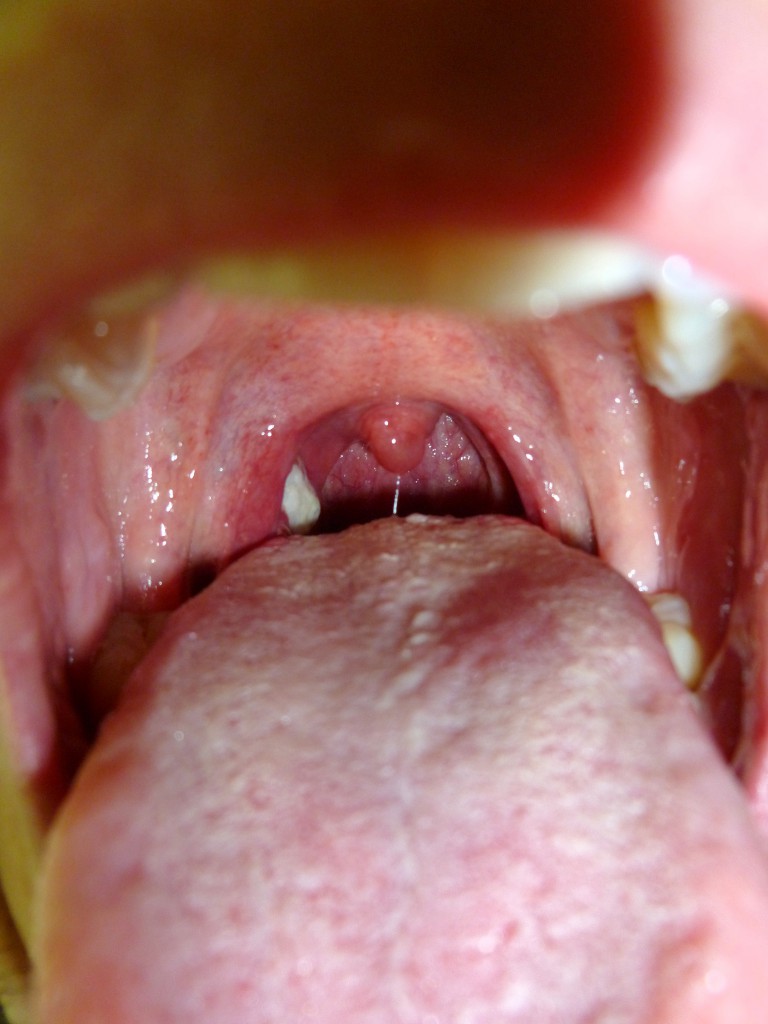

Unschwer ist der weisse Fleck zu erkennen. Das ist genau der, der mich beim Schlucken immer so sticht! Zum Glück nur, wenn ich schlucke, nicht er.

Besonders abstossend ist auch dieser eklige Speichelfaden am Halszäpfchen. Alles in Allem ein sehr wüstes Bild.

Mit viel Geduld. Es handelte sich um das Pfeiffer’sche Drüsenfieber (http://de.wikipedia.org/wiki/Pfeiffer-Dr%C3%BCsenfieber), welches man bloss mit viel Zeit und ohne Antibiotika wegkriegt. Ich hatte aber Glück und war nur etwa zwei Wochen ausser Gefecht. Ich habe von anderen Pechvögeln gehört, die ein halbes Jahr ans Bett gefesselt waren …